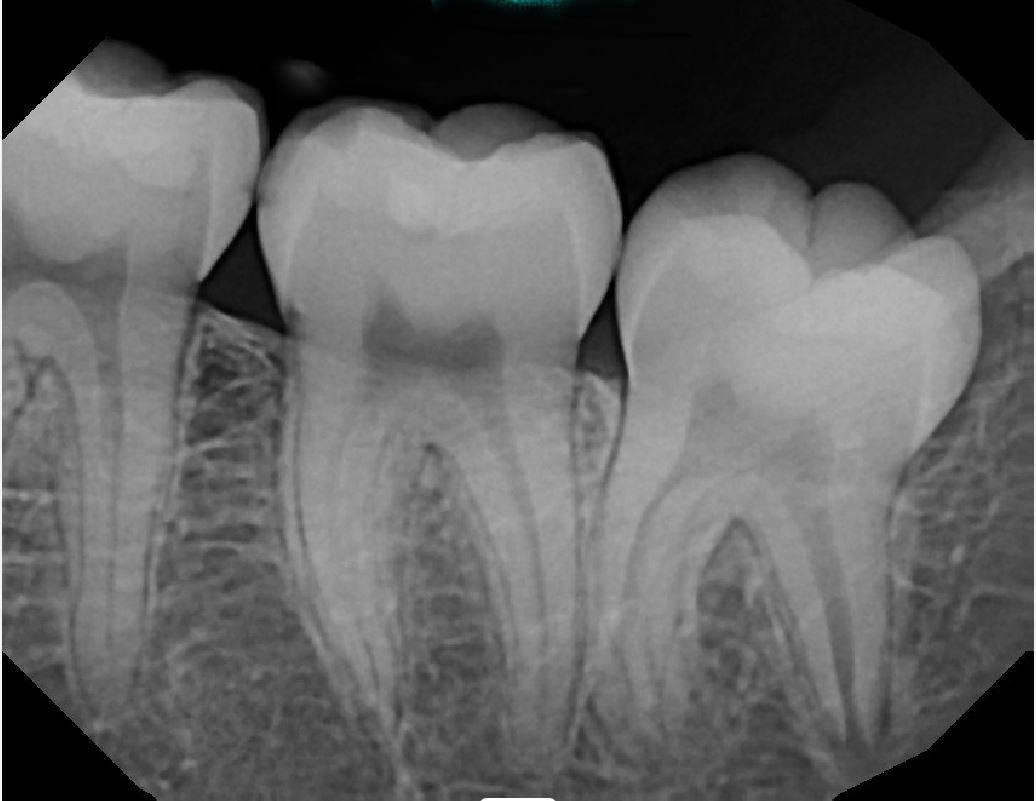

X-Ray 3: How many caries are present?

(Required)

X-Ray 3: How many PAP's are present?